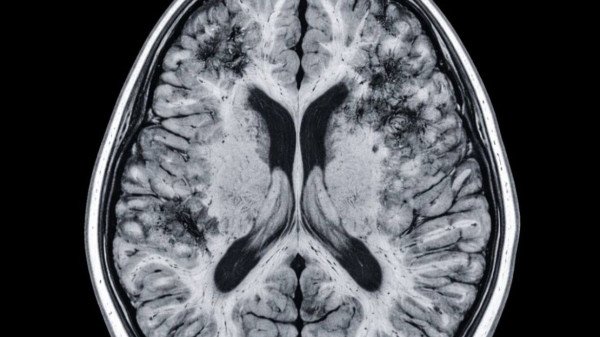

Mais de 55 milhões de pessoas no mundo vivem com algum tipo de demência. Uma pesquisa conduzida na Universidade de Harvard pelo neurologista Rudolph E.